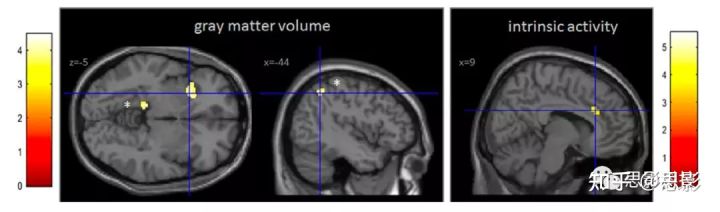

图1 GMV的两组比较

左图:与对照组相比,SPA患者的GMV存在差异。左侧前岛叶和左侧PHC的GMV较低。SPA患者左缘上回GMV增加。*表明这些区域在BDI评分共变异中没有存活。所示为二级ANCOVA结果,p < 0.001未经校正的身高,k > 80体素。

右图:与对照组相比,SPA患者的内在活动存在差异。SPA患者右侧ACC活性较低。所示为二级ANCOVA结果,p < 0.001,未校正,k > 5个体素。颜色条表示t值。

- 3.2 灰质体积GMV

与对照组相比,SPA患者在左侧前岛叶(x = 27, y = 17, z =−5, Z = 3.68, k = 326),左侧下颞叶(x = −27, y = −9, z = −48, Z = 3.99, k = 176),左侧海马旁皮质(PHC, x = −14, y=−36, z =−3, Z = 3.90, k = 197)的GMV减小;在左侧边缘上回皮层(x = −44, y = −75, z = 9, Z = 3.91, k = 138)的GMV增大。如图1所示。

- 3.3 ALFF

与对照组相比,SPA患者右侧ACC的ALFF较低(x = 9, y = 27, z = 27, z = 4.72, k = 14体素);参见图1。与对照组相比,在SPA中没有发现ALFF增加的区域。